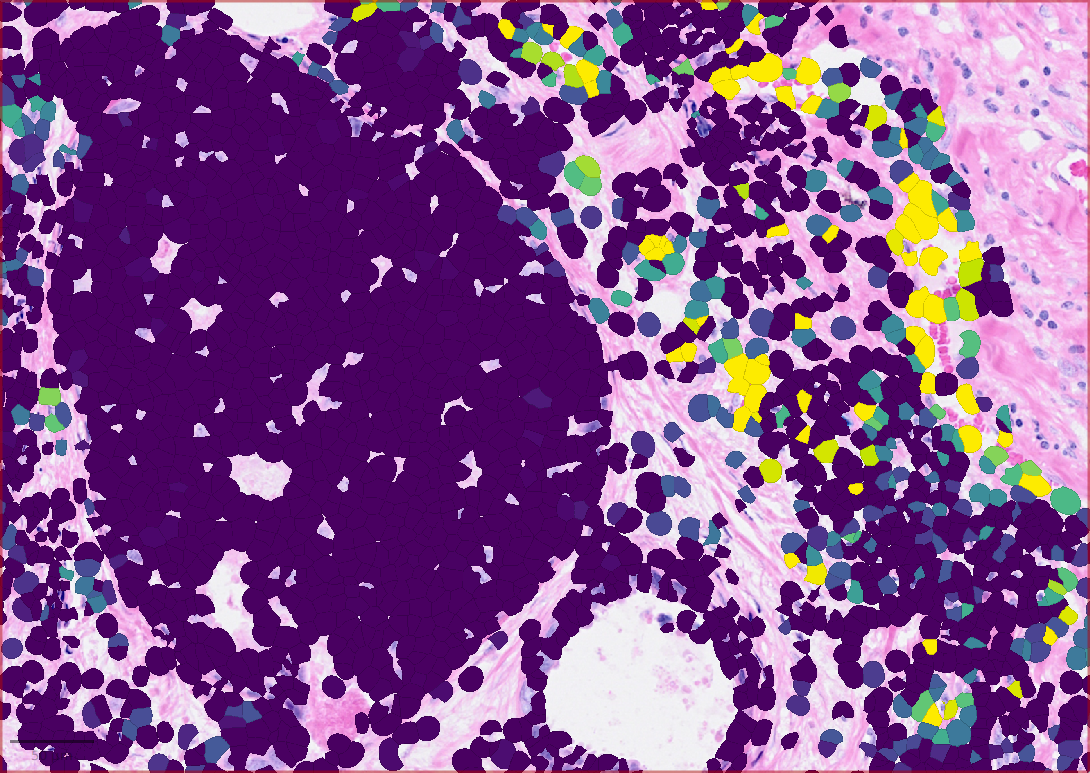

Refer to caption

(a) Neighboring cell connectivity

(b) Distance to the boundary of a specific cell-type cluster

(c) Cell-cell interaction: MMP2->PECAM1

(d) DBSCAN-CellX based cell clustering

Figure 2: Results showing some functions provided by QuST: (a) Neighboring cell connectivity based on Delaunay clustering. Various single cell analyses available in QuST are based on the neighboring cell connectivity. (b) QuST’s cellular spatial profiling generates a heat map indicating the distance to boundary of a specific cell type, e.g., tumor epithelial cells to the corresponding tumor boundary. (c) The heat map showing the cell-cell interaction intensity of the given LR pair, e.g., MMP2->PECAM1. (d) Result of QuST’s DBSCAN-CellX implementation.

The results showing in Figure 2 represents some comprehensive analyses of the experimental data using a range of powerful functions provided by QuST. First, given the fact that many spatial biological analyses rely on cellular spatial analysis, the Delaunay clustering method implemented in QuPath is employed to generate neighboring cell connections. For example, QuST’s cellular spatial profiling, which generates a heat map that indicates the boundary distance of individual cells, e.g., the distance from a cancer epithelial cell to the boundary of the corresponding tumor boundary. Based on the heat map, one can explore the differential gene expression patterns between the intratumoral tumor cells and the tumor cells present in the immune-invasive region, which are located on the surface of the tumor. Next, QuST’s LR-product method offers an additional layer of analysis by generating a heat map that illustrates the intensity of cell-cell interaction for a specific LR pair. This heat map provides a quantitative measure of the strength and significance of communication between specific pairs of cells. Finally, a result of QuST’s DBSCAN-CellX implementation is shown, which provides a comprehensive understanding of spatial relationship of the chosen cell clusters.